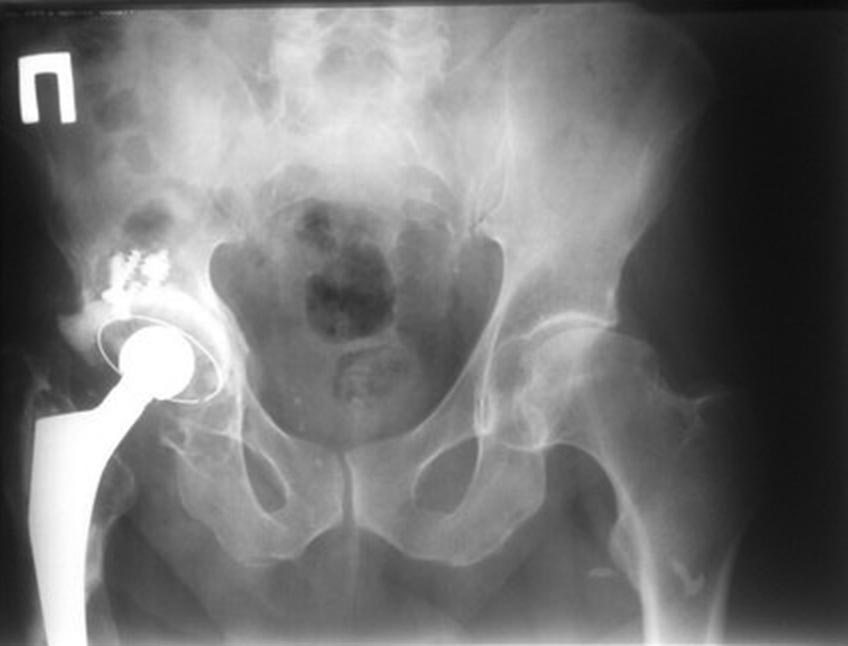

надо бы сделать снимки качественные на протяжении всего диафиза- ниже ножки тоже кажется какие-то очаги, исключить метастазы, спланировать какой протез брать- возможно на Вагнеровской ножке.

Нужно ревизовать ножку эндопротеза, хоть вагнером, хоть СЛР-кой, лучше - в специализированном центре. Можно хоть к нам, в Курган.